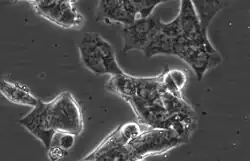

LAPC4

LAPC4 cells are a cell line of human prostate cancer commonly used in the field of oncology. The tissue was harvested from the lymph node metastasis of a male patient with hormone refractory prostate cancer which was then xenografted into SCID mice and later harvested and plated on tissue culture dishes, where it can be propagated as an immortalized prostate cancer cell line.[1][2][3]

Characteristics

LAPC4 are a lowly adherent, epithelial cell line with high Androgen receptor and Prostate specific antigen expression.[4] Unlike the other commonly utilized, Androgen receptor positive prostate cancer cell lines LNCaP and VCaP, LAPC4 have high expression of Keratin 5, a basal marker, as well as the luminal markers Keratin 8 and Keratin 18.[4] LAPC4 also expresses mutated P53 (R175H). [4]

The cells have an approximate doubling time of 72 hours under typical culture conditions.[5]